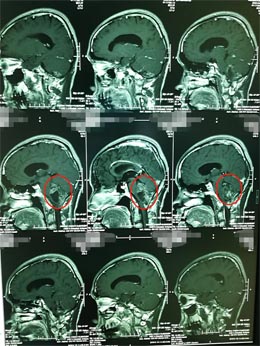

▲术前MR

肿瘤来源于四脑室底,与脑干关系密切。第四脑室是一个非常重要的解剖区域,腹侧毗邻桥脑、延髓等脑干结构,又是脑室系统内脑脊液循环通路的最后环节,由于瘤体周围有重要的神经、血管组织,故手术对肿瘤进行彻底切除难度较大。目前情况下,手术仍是首选的治疗方法。